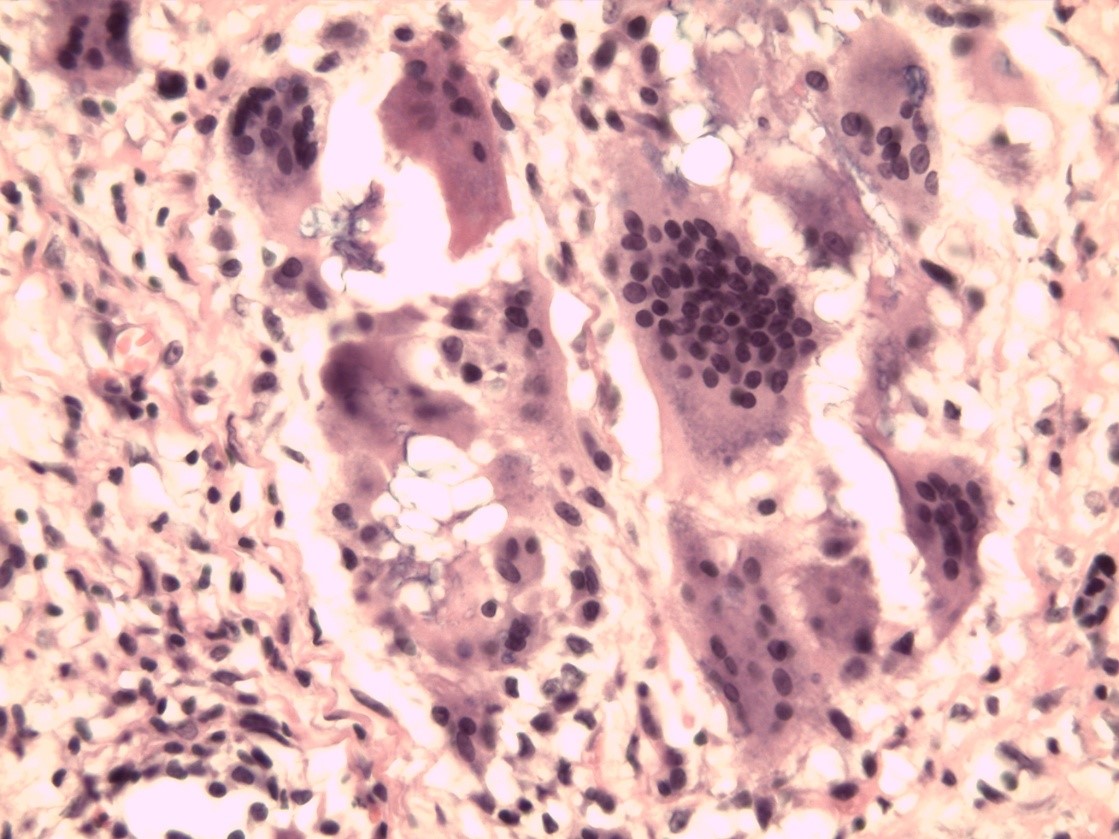

В подавляющем большинстве наблюдений поздних осложнений «гелевой» болезни (6 пациенток) гистограмма расценена как хроническое продуктивное воспаление различной степени выраженности, несмотря на клиническую картину острого воспалительного поражения. Оно проявлялось присутствием эпителиоидных и гигантских многоядерных клеток инородных тел с овальными гиперхромными ядрами, лимфоцитов и плазматических клеток практически по всей зоне гелевой аугментации (рис. 4). Самое большое количество гигантских клеток визуализировали в паренхиме МЖ на границе с гелем. Встречались даже единичные клетки Пирогова–Лангханса, характеризующиеся периферическим расположением овальных ядер. Наличие микроабсцессов в 2 наблюдениях говорило о деструкции соединительной ткани, обусловленной в том числе токсическим влиянием ПААГ. Как в первичном очаге, так и в зонах миграции обнаруживали гелеомы в виде межклеточных скоплений ПААГ, окруженные плотной капсулой из коллагена, фибробластов и гигантских многоядерных клеток. Размеры данных образований могли существенно отличаться друг от друга даже в пределах одной зоны (рис. 5). Железистая ткань МЖ в отдаленном периоде после порочной пластической операции у 100% больных была с выраженным склерозом, дистрофией и атрофией долькового аппарата; очевидно замещение последнего клетками жировой ткани. Следует отметить, что при длительном сроке залегания геля инволютивные изменения железистого аппарата (фиброз и облитерация паренхимы) у лиц старше 50 лет носили более выраженный характер, чем ожидаемые в данной возрастной категории.

Рис. 4. Биоптат ткани молочной железы: гигантские клетки инородных тел. Окраска гематоксилином и эозином (×400).